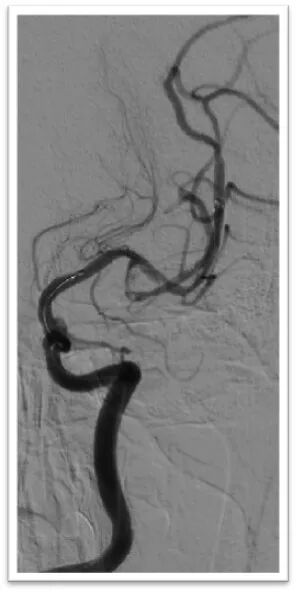

图4:DSA提示主动脉弓为牛角弓,左侧颈总动脉发自头臂干动脉,右侧颈内动脉造影提示前交通动脉开放,呈双干大脑前动脉,左侧大脑前动脉通过软膜支向左侧大脑中动脉供血区域代偿,双侧椎动脉均势供血,左侧大脑后动脉通过软膜支向前代偿供血;左侧颈总动脉闭塞,残端呈杯口状,近端可见白色血栓影,初步考虑栓塞性闭塞。